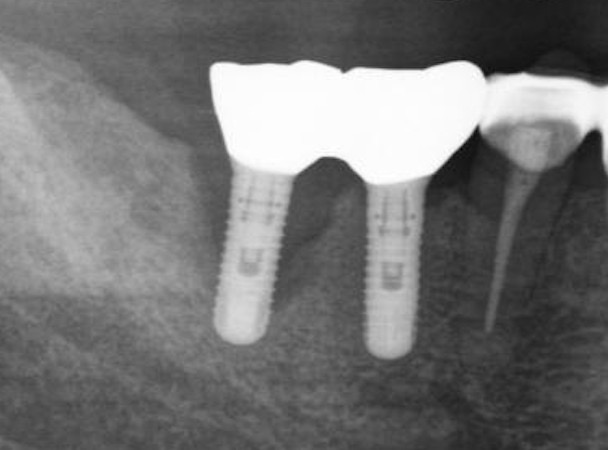

来院時

当院来院時のレントゲン

当院来院時

他院で「インプラントの撤去とやり直しが必要」と診断され、当院を紹介されて来院された時の状態です。